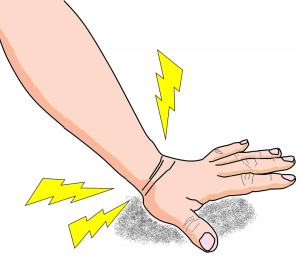

外傷:橈骨遠位端骨折

▶ 症状、受傷の仕方

手首の周辺の痛み、腫れ、変形が生じ、手首を動かすと痛みが生じます。転倒、転落により手首を強く地面と着くことで受傷します。骨粗鬆症が有る場合、立っている高さからの転倒でも生じることがあります。

▶ 病態